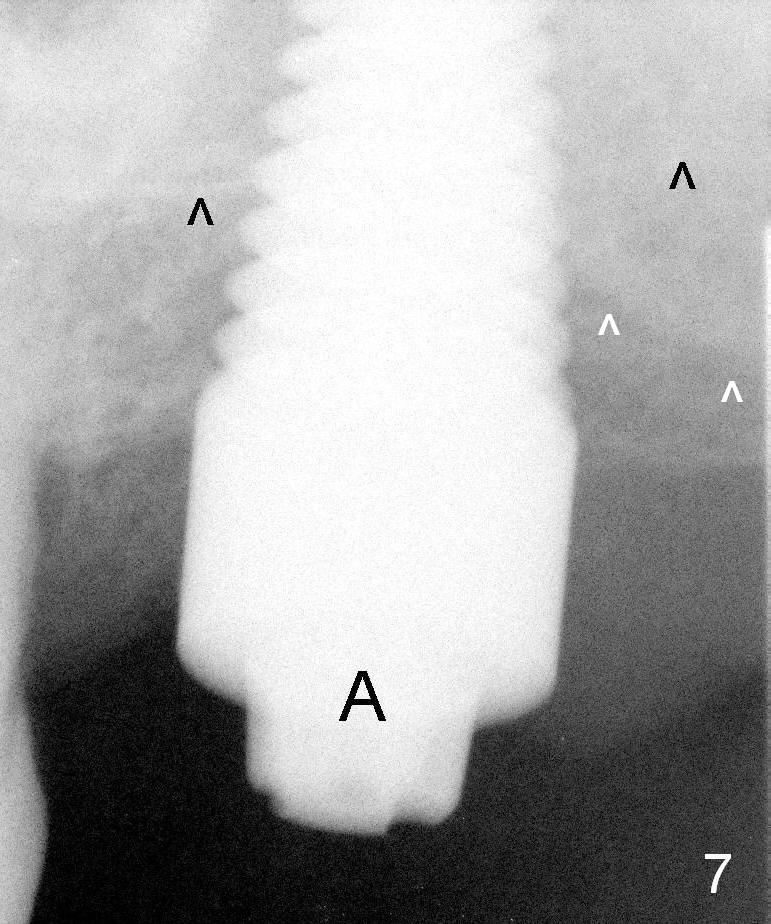

The bone looks normal around the implant 4.5 months postop (Fig.7) except buccodistally (white arrowheads). It appears that the oversized implant aggravates buccal plate defect postop.